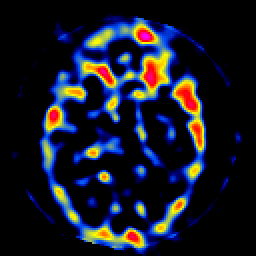

SPECT TL Study #8 -- Slice #23